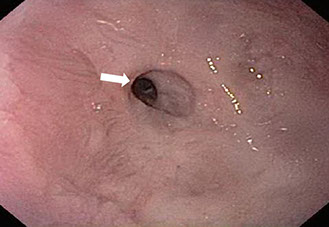

Lesión de Dieulafoy

Es una anomalía vascular localizada generalmente en estómago proximal y consiste en la presencia de una arteria de gran calibre en la submucosa y ocasionalmente en la mucosa, aunque el diagnóstico definitivo es anatomopatológico, con la endoscopia se puede alcanzar una precisión elevada.